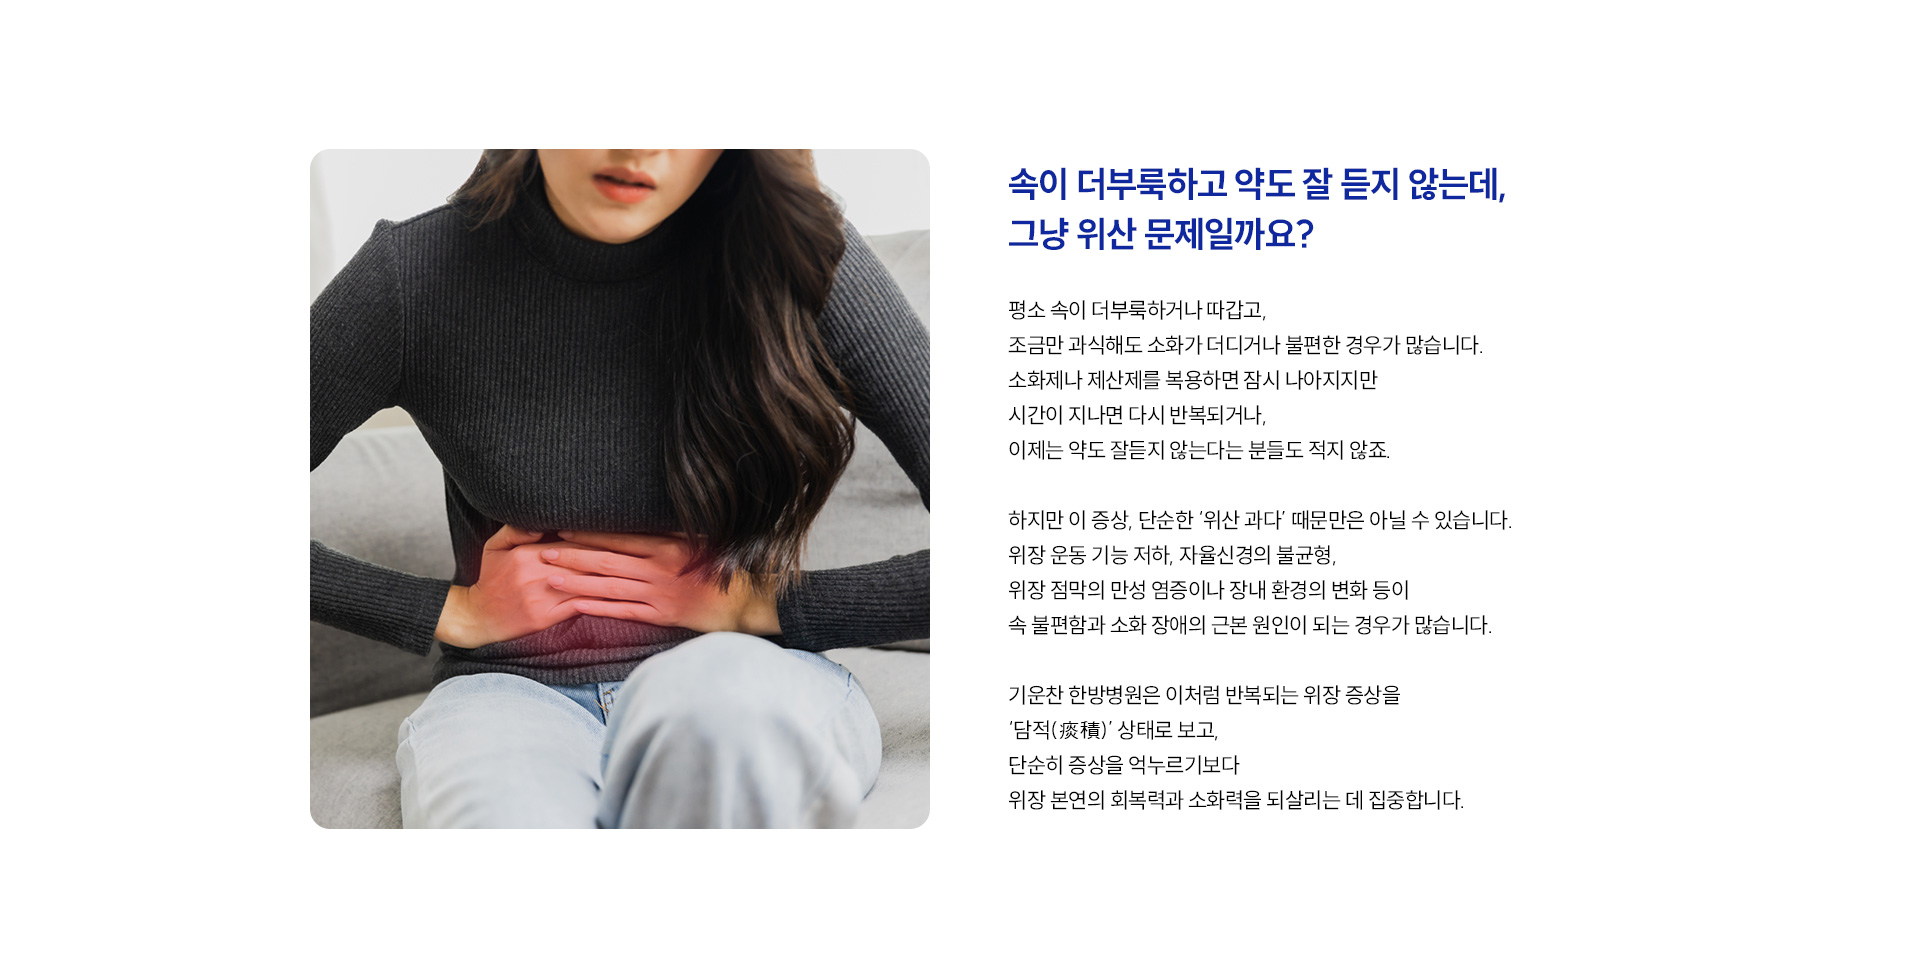

계속 반복되는 소화불량, 한방 치료로 해결할 수 있을까요?

네, 담적은 위장의 운동 기능 저하, 기혈 순환 정체, 자율신경계 불균형 등의 기능 이상을 의미합니다.

1.담적을 배출, 2. 위장운동력을 회복, 3. 자율신경 안정과 회복을 돕습니다.